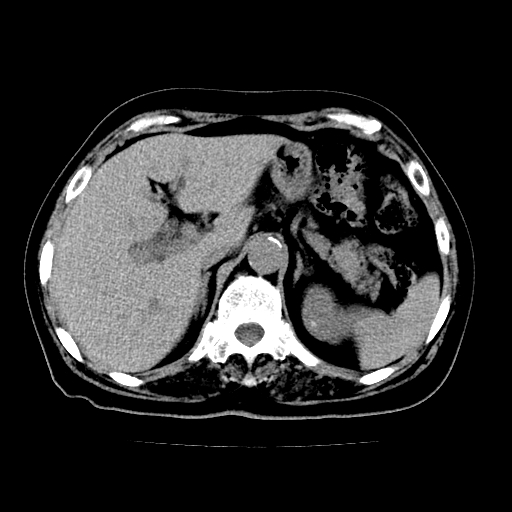

以下是引用zsl6918在2009-2-7 22:12:00的发言:[br]结合临床支持胰腺炎,建议强化查明胆总管扩张的原因。

以下是引用zsl6918在2009-2-7 22:12:00的发言:[br]结合临床考虑胰腺炎可能,建议强化查明胆总管扩张的原因。